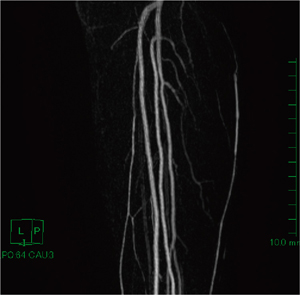

そこで,腓骨動脈から分岐する末梢動脈の描出法として,造影MRAを行った(図5)。MRAは,骨の影響を受けずに血管を描出できることが最大の特長である。しかも,造影MRAは,データ収集方法がCTとは異なるため,動脈血管だけを選択的に描出でき,本症例のような形態を把握するのには大変有用だと考える。しかし,MRAでは骨の情報が乏しいために,骨周辺の血管走行が不明瞭なのが問題点となる。

図5 症例2:下腿部の造影MRAのMIP(maximum intensity projection)像

撮像条件は,3D-T1-TFE法にて下腿部を矢状断像で撮像し,撮像コイルは32ch cardiac torso coilを使用した。Gd造影剤を注入速度3mL/sで注入し,造影後から造影前を差分することで血管を描出する方法を用いた。また,目的血管が筋肉内を走行する穿通枝動脈であるため,循環器内科医の協力のもと,亜硝酸剤スプレーを用いた。高速注入と血管を拡張させていることで,腓骨動脈から分岐する穿通枝動脈が明瞭に描出されている。